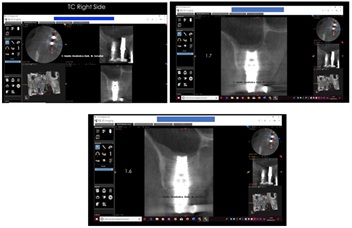

TC right side shown in figure 31.

Figure 31: TC Right Side.